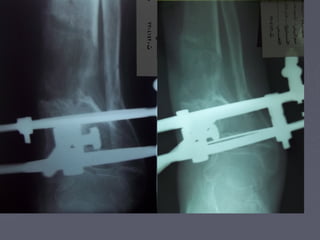

Proximal Tibial Osteotomy

•In the procedure to realign the

angles, a wedge of bone is

removed from the lateral side

of the upper tibia.

•A staple or plate and screws

are used to hold the bone in

place until it heals.

•This converts the extremity

from being bow-legged to

knock-kneed.

•The Proximal Tibial Osteotomy buys some time before ultimately

needing to perform a total knee replacement. The operation

probably lasts for 5-7 years if successful.